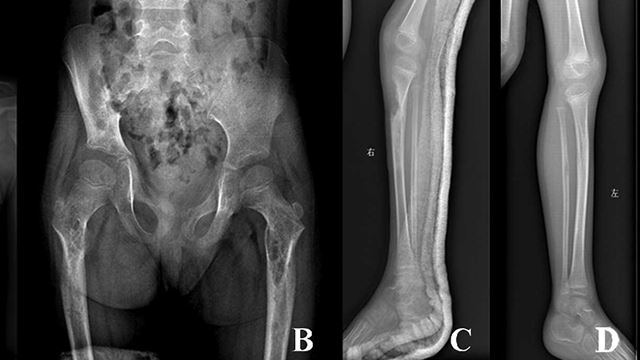

Penyakit Tulang Hilang Tiba-Tiba, Doktor Masih Tiada Jawapan